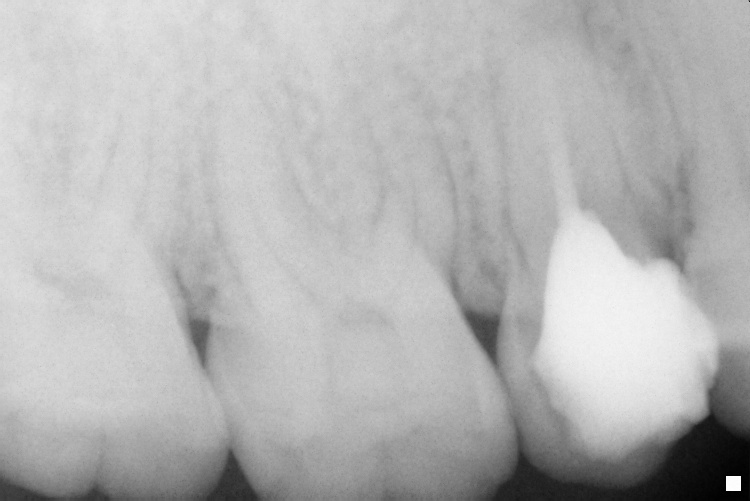

Name Last modified Size Description Parent Directory - IO000001.jpg 2020-07-28 14:17 78K IO000002.jpg 2020-07-28 14:17 78K IO000003.jpg 2020-07-28 14:17 81K IO000004.jpg 2020-07-28 14:17 76K